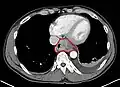

Esophageal cancer (lower part) as a result of Barrettʼs esophagus